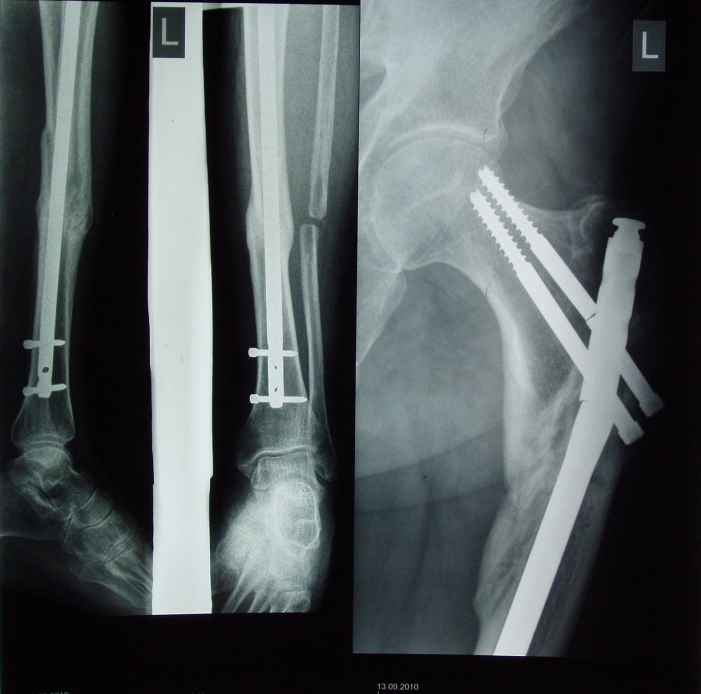

Перелом стержня и винтов в верхней трети бедра, ложный сустав |

Доброго времени суток, уважаемые коллеги. Хочу представить вашему вниманию ситуацию в которой мы оказалисти. 1,5 года назад данному пациенту было произведено штифтование методом БИОС при переломах средней трети большеберцовой кости и верхней трети бедренной кости левой нижней конечности. В раннем послеоперационном периоде больной оказался вне нашего внимания,и через 6 месяцев после синтеза была произведена резекция малоберцовой кости, туннелизация областей переломов, динамизация стержней, компрессирование перелома большеберцовой кости с помощью заглушки. В динамике больной активно пользовался конечностью. В области перелома большеберцовой кости достигнуто сращение. В сентябре в области левого бедра больной услышал хруст, обрасти внимание на боли при ходьбе в области перелома. При осмотре у больного отмечено укорочение укорочение левой нижней конечности до 4 см. На рентгенограммах определяется перелом винтов и верхней трети гвоздя, смещение в чрезвертельной области, изменение оси бедра.Больному предстоит операция реостеосинтеза, уважаемые коллеги, мнения докторов в выборе метода операции разошлись. DHS, перештифтование, PFN. Хочется услышать ваши мнения. Заранее благодарим. К сожалению все снимки на данный момент предоставить не можем.

Я думаю, что причина проблемы в том, что гвоздь в бедро введен "непростительно латерально." Но, все равно непонятно откуда 4 см укорочения? Или это функциональное, за счет контрактуры? Мое мнение - надо перештифтовать из нормального входа в канал.

Установленный реконструктивный стержень может введен и латерально, хотя не факт, что поломка конструкции наступила при тех обстоятельствах о которых говорит больной. У меня совсем недавно тоже был клиент, у которого сначала хрустнуло и стало больно, а в итоге выяснилось, что он пьяный упал в яму(там стержень выдержал,но появилась импрессия мыщелка б/б кости). Здесь мне кажется более оптимально любой вертельный стержень (Гамма, PFN, PFN-I и т.д.) из этого же входа. А DHS? думаю нет, всётаки укреплять надо не вертельно-шеечный, а подвертельный компонент.

Поддерживаю тактику. Только я бы не брал снова ChM. У него за счет "универсальности" слишком ослаблен проксимальный конец. Взял бы любой проксимальный или реконструктивный стержень с толстой "головой" в длинной версии.

Однозначно штифт с изменением точки введения, лучше все таки гамма но лучше длинную, дабы не рисковать в дальнейшем с периимплантным переломом